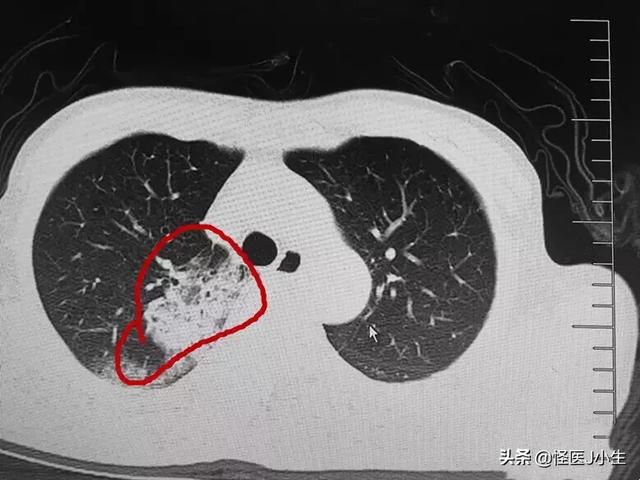

2. die Bildgebung:Röntgenaufnahmen der Brust und CT-Aufnahmen der Lunge können fleckige Schatten in der Lunge zeigen, die in den äußeren Bändern der Lunge zu erkennen sind, und in schweren Fällen können solide Schatten in der Lunge zu sehen sein.

iii,Es wurde ein CT des Brustkorbs durchgeführt, um zu bestätigen, dass eine Person in der Vergangenheit einer Neokoronavirus-Pneumonie ausgesetzt war, ohne dass signifikante Symptome wie Fieber und Husten vorlagen.Die endgültige Diagnose einer Neokoronavirus-Pneumonie kann gestellt werden, wenn das Ergebnis darauf hindeutet, dass mehrere flockige Mongolenschatten in beiden Lungen vorhanden sind und ein Rachenabstrich mit neuartigem Coronavirus-Nukleinsäuretest positiv ausfällt.